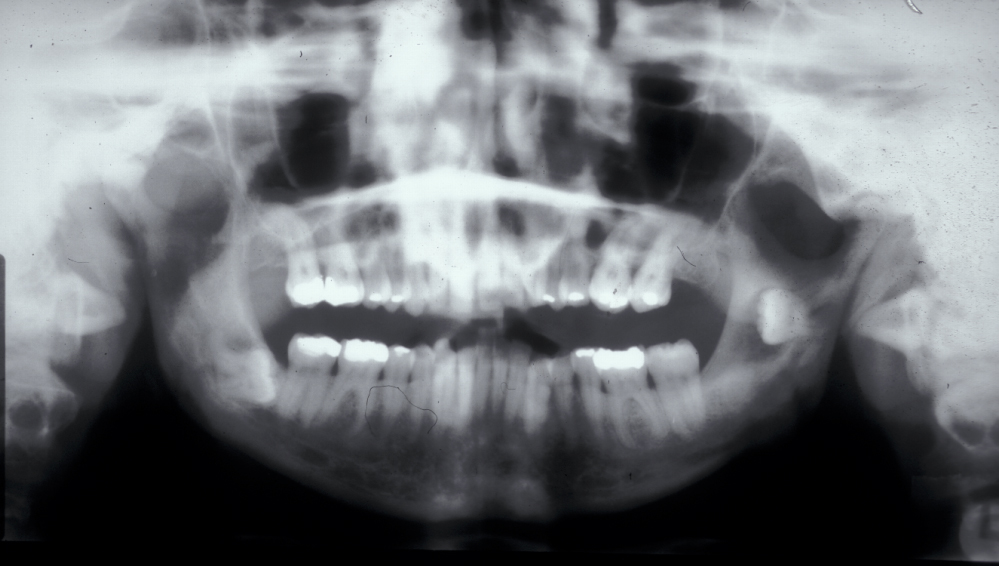

Figure 2 and Figure 3 illustrate examples of indications for removal of a third molar tooth.

Assessment of the tooth is both clinical and radiographic. If somebody presents in pain, it is important to establish that this is coming from the third molar and not elsewhere. Pain is often vague, poorly localised and may be referred from another tooth, or as part of facial arthromyalgia (condition affecting the jaw joint). A dental panoramic radiograph is ideal as it helps to assess all the teeth at once. The health of the adjacent molars may influence the decision whether to remove the third molar or not. Large crowns or old restorations are all at risk of dislodgement during surgery. It is also worth considering whether alternative treatment options are available. For instance, pericoronitis due to an over-erupted upper third molar may be dealt with by extracting that tooth only, with or without operculectomy. In the presence of other teeth of poor prognosis, will it be better in the long term to save the third molar which may be used as a denture or bridge abutment in the future?

These points help to determine whether the tooth can be simply elevated or will need a surgical approach. A series of radiographs depicted in Figure 4 to Figure 8 illustrate these points further.